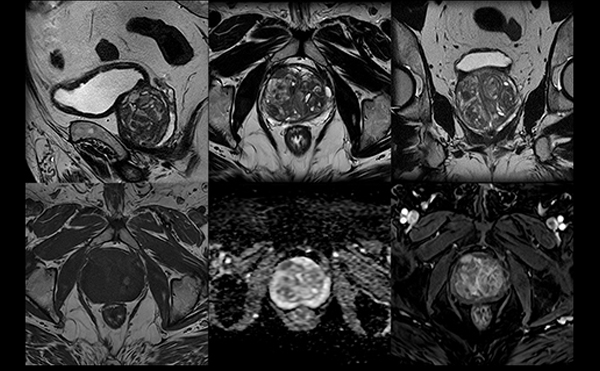

Magnētiskās rezonanses (MR) izmeklējums prostatai tiek veikts, lai detalizēti izvērtētu prostatas struktūru un patoloģiskas izmaiņas.

PI-RADS ir sistēma, ko radiologi izmanto, lai novērtētu prostatas MR attēlos redzamās izmaiņas un noteiktu, cik lielā mērā tās varētu būt saistītas ar prostatas vēzi.

PI-RADS vērtējums tiek izteikts ar ciparu no 1 līdz 5:

PI-RADS 1–2 nozīmē, ka ļaundabīga procesa iespējamība ir ļoti zema,

PI-RADS 3 – neskaidra atrade,

PI-RADS 4–5 – paaugstināta iespējamība, ka atradums varētu būt vēzis.

Svarīgi saprast, ka PI-RADS vērtējums pats par sevi nav diagnoze – tas tikai norāda, cik liels ir ļaundabīga procesa risks. Galīgo apstiprinājumu sniedz biopsija vai histoloģiska analīze.